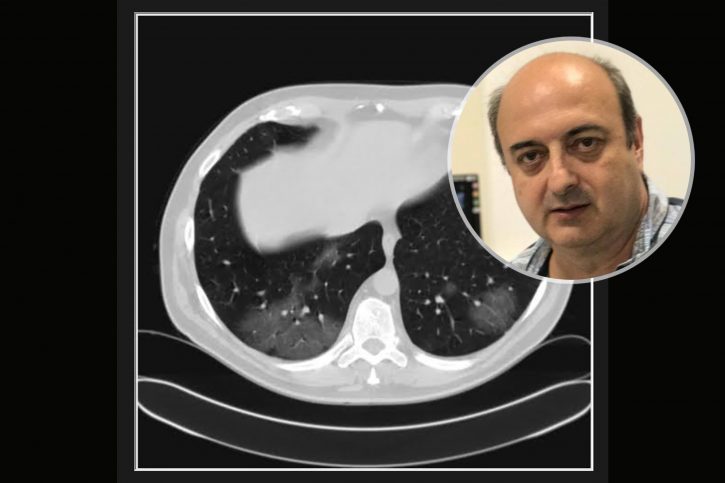

Pacijent prvi put dolazi 3 dana nakon pojave simptoma a dva dana nakon pozitivnog testa. Ima temperaturu koja tek prelazi 37. Ne kašlje, testirao se kao kontakt. Oseća mirise i ukuse. Po laboratoriji pulmolog koji ga je pregledao misli da je moguće da se radi o nekom novom soju. Nije vakcinisan. Nije ni antivakcinaš. Jednostavno je mislio da sačeka.

Severity score 0/25. Najdraže mi je kada vidim to.